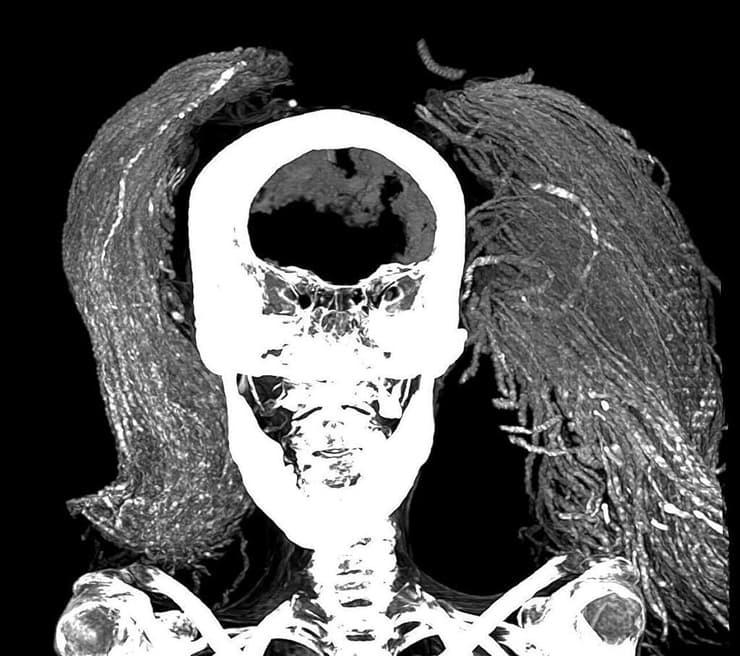

במחקר החדש, פרופ' סאלים השתמשה בסריקות CT כדי לנסות ולחשוף את גילה של האישה, לזהותה מבחינה פתולוגית ולאמוד את מצב השימור של המומיה. יחד עם האנתרופולוגית ד"ר סמיה אל-מרגני ממשרד התיירות והעתיקות של מצרים, השתמשו השתיים במספר טכניקות מתקדמות, באמצעותן גילו שמצב השימור של המומיה טוב ביחס לזמן הרב שחלף.

מתמונות CT דו-ממדיות ותלת-ממדיות, עולה כי גובהה של האישה הצורחת היה 1.54 מטר בחייה. לפי המורפולוגיה של המפרק בין שתי עצמות האגן, העריכו החוקרות כי היא הייתה כבת 48 במותה. כמו כן, התגלה כי האישה הצורחת סבלה מדלקת פרקים קלה בעמוד השדרה, זאת על בסיס נוכחותן של בליטות גרמיות (אוסטאופיטים) על החוליות.

פרופ' סאלים ועמיתתה למחקר לא מצאו חיתוכי חניטה, מה שעולה בקנה אחד עם הגילוי שהמוח, הסרעפת, הלב, הריאות, הכבד, הטחול, הכליות והמעי נמצאים במקומם. זו הייתה הפתעה, שכן שיטת החניטה הקלאסית בממלכה החדשה (1550-1069 לפנה"ס) כללה הסרה של כל האיברים הללו, מלבד הלב.